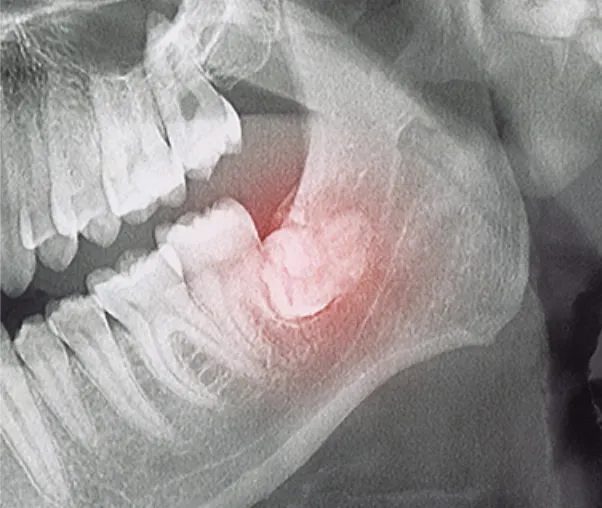

사랑니의 뿌리는 신경과 가까운 경우가 많아, 발치 전 신경 손상 가능성에 대해 철저히 분석한 뒤 손상이 없도록 정밀한 치료를 진행해야 합니다.

신경과 턱뼈의 손상 우려

뼈 속에서 사랑니가 자라는 경우 종양발생의 위험이 있으며, 신경과 턱뼈의 손상을이 일어날 수 있어 부작용에 더욱 주의해야 합니다.

사랑니 뿌리근처에는 아래턱 신경이라는 커다란 신경이 지나갑니다. 개인마다 다르지만 뽑는 과정에서 신경에 손상을 일으킬 가능성이 있습니다. 신경손상 가능성에 대한 사전 분석이 필요하며 손상 가능성이 있다고 판단되는 경우 경험 많은 의사에게 조심스러운 발치 및 후 처리가 요구됩니다.